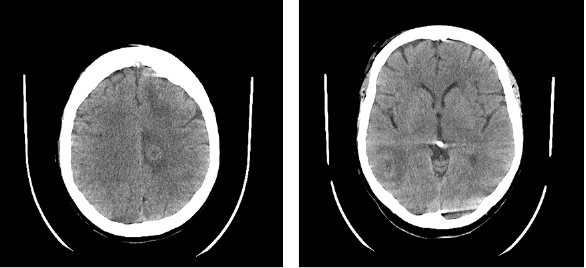

In November 2023, a 55-year-old female patient was hospitalized following a fall at home which resulted in a left elbow fracture. The patient had been feeling dizzy before the incident, prompting a head CT to exclude a head trauma and determine the cause of the dizziness. The CT revealed multiple brain lesions, with differential diagnoses including metastases and abscesses (Fig. 1), necessitating further evaluation via magnetic resonance imaging (MRI). The patient’s medical history indicates that she had been diagnosed with seropositive myasthenia gravis in July 2015. The diagnosis was confirmed by the presence of positive antibodies against acetylcholine receptors (AChR), and a muscle biopsy was performed. The patient was taking Mestinon 60mg x 3, Prednisolone 5mg x 1, and Azathioprine 50mg x 2 for treatment. Plasmapheresis was used to treat exacerbations of myasthenia gravis.

Fig. 1. Head CT scan. Multiple foci with perifocal edema in the brain – differentiate between metastases and abscesses (less likely to be abscesses)